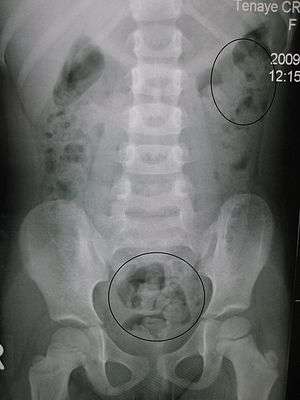

| Constipation in a young child as seen by X-ray. Circles represent areas of fecal matter (stool is opaque white surrounded by black bowel gas). | |